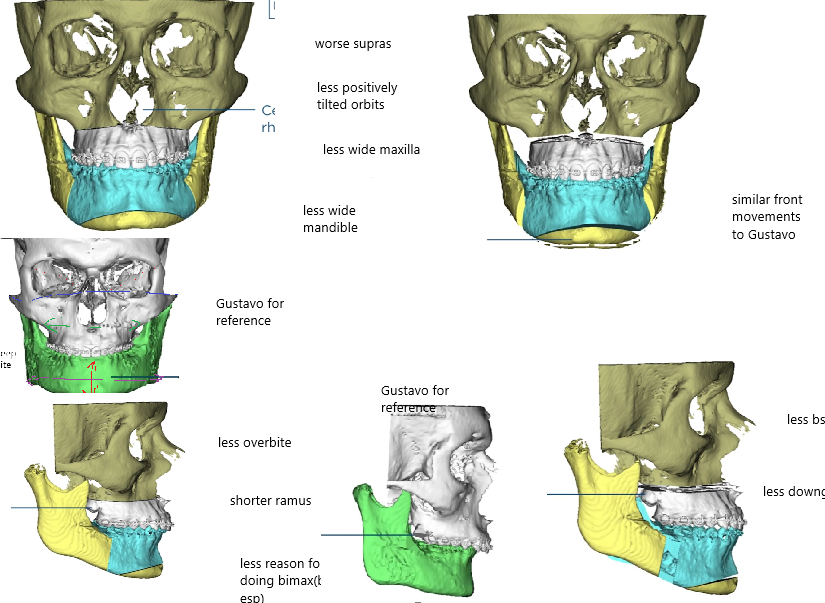

Lets now look at another alfaro case which didnt have equally good ascension, but he still had a sfs.

As we can see from the front he didnt have as much of a overbite or retrusion.

Because he didnt have much recession the lower jaw didnt became more vertically long as it wasnt hidden away behind a huge overbite or deep bite as in gustavos case. But he did a vertical genio which i think was a mistake

lets look at his bones and compare to gustavos:

Lets now look at another alfaro case which didnt have equally good ascension, but he still had a sfs.

As we can see from the front he didnt have as much of a overbite or retrusion.

Because he didnt have much recession the lower jaw didnt became more vertically long as it wasnt hidden away behind a huge overbite or deep bite as in gustavos case. But he did a vertical genio which i think was a mistake

lets look at his bones and compare to gustavos: